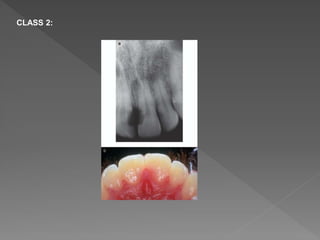

CLASS 2:

• #50 Class 1 – Denotes a small invasive resorptive lesion near the cervical area with shallow penetration into dentine. Class 2 – Denotes a well-defined invasive resorptive lesion that has penetrated close to the coronal pulp chamber but shows little or no extension into the radicular dentine. Class 3 – Denotes a deeper invasion of dentine by resorbing tissue, not only involving the coronal dentine but also extending into the coronal third of the root. Class 4 – Denotes a large invasive resorptive process that has extended beyond the coronal third of the root.